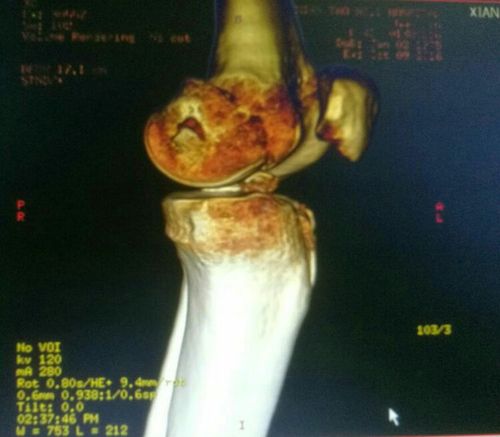

股骨内侧髁骨折,胫骨平台骨折,髁间嵴撕脱骨折.

股骨髁骨折

髁间棘骨折

胫骨髁间骨折图片

胫骨髁间棘骨折图片

胫骨髁间骨折

胫骨髁间棘撕脱性骨折

胫骨髁间隆突骨折

胫骨髁骨折